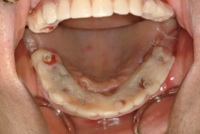

一日も歯がないという状態はありません。 この写真の方も前歯しか残っていませんが、インプラント手術当日まで前歯は残しておいて、その当日に抜歯、インプラントを入れて仮歯を固定しています。つまり、歯は一日で入るので、歯が無い、見た目が悪いという状態は全くありませんので、ご心配なく。大分県大分市スマイルライン歯科ではオールオンフォー(all- on- 4)の治療を全国でもいち早く行い数多くの症例を手掛けてきました。そして治療を行ったすべての患者様に喜んで頂いておりますのでご希望の方はまず、CTレントゲンなどで骨の形を診査しますのでお問い合わせください。

その日入った仮歯です、もちろん固定式で、入れ歯のような取り外しは当日から必要ありません。